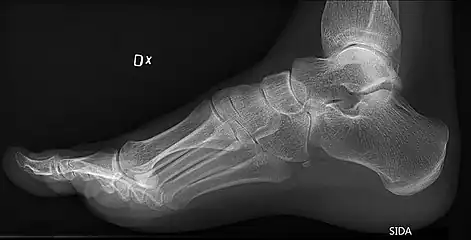

On weightbearing projectional radiography, pes cavus can be diagnosed and graded by several features, the most important being medial peritalar subluxation, increased calcaneal pitch (variable) and abnormal talar-1st metatarsal angle (Meary's angle).[17] Medial peritalar subluxation can be demonstrated by a medially rotated talonavicular coverage angle.[17]

Same lateral X-ray showing the measurement of Meary's angle, which is the angle between the long axis of the talus and first metatarsal bone.[17] This example is slightly convex downward. An angle greater than 4° convex upward is considered pes cavus.[17]

Foot with pes cavus (and os peroneum).